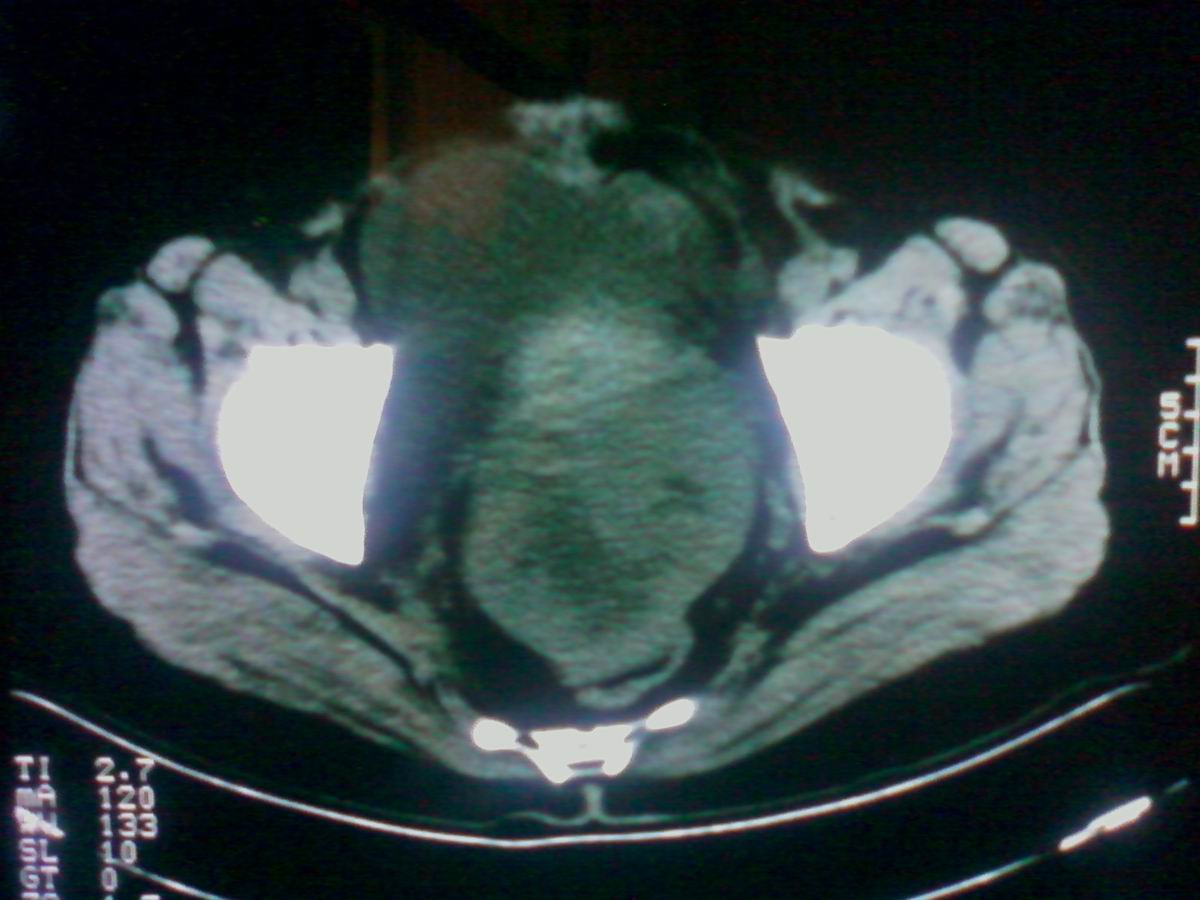

标题: CT25799:女性患者,45岁,腹胀,上腹部疼痛来诊,B超示盆腔 [打印本页]

标题: CT25799:女性患者,45岁,腹胀,上腹部疼痛来诊,B超示盆腔

考虑卵巢癌伴腹水

1)考虑卵巢恶性肿瘤。2)腹水。